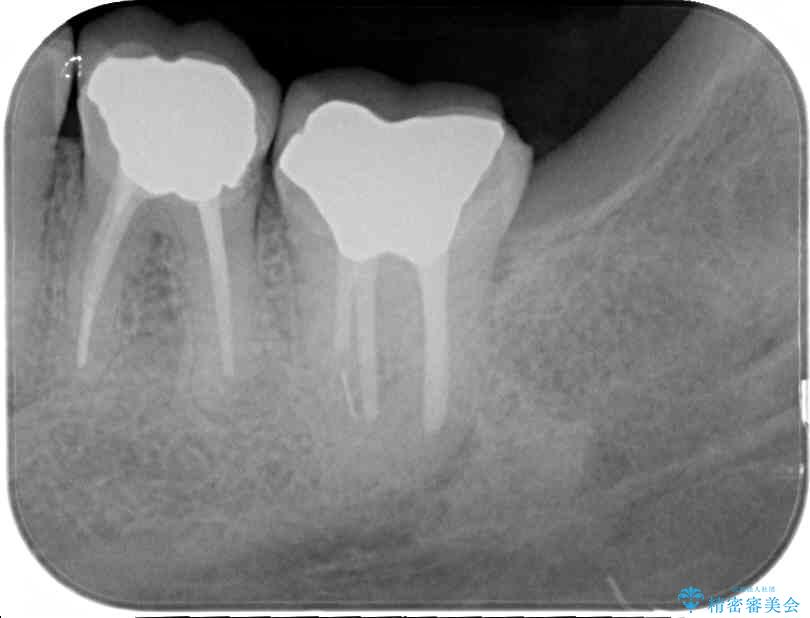

下顎の1番奥の歯であり、歯肉に覆われている部分が大きいためセラミックの十分な厚みが取れない状態でした。

強化セラミックを用いたオールセラミッククラウンにて補綴治療を行うこととしました。

十分な土台の高さを確保できない状態であったので、維持力のある土台の形態に整えることで、極力長持ちする治療を心がけました。